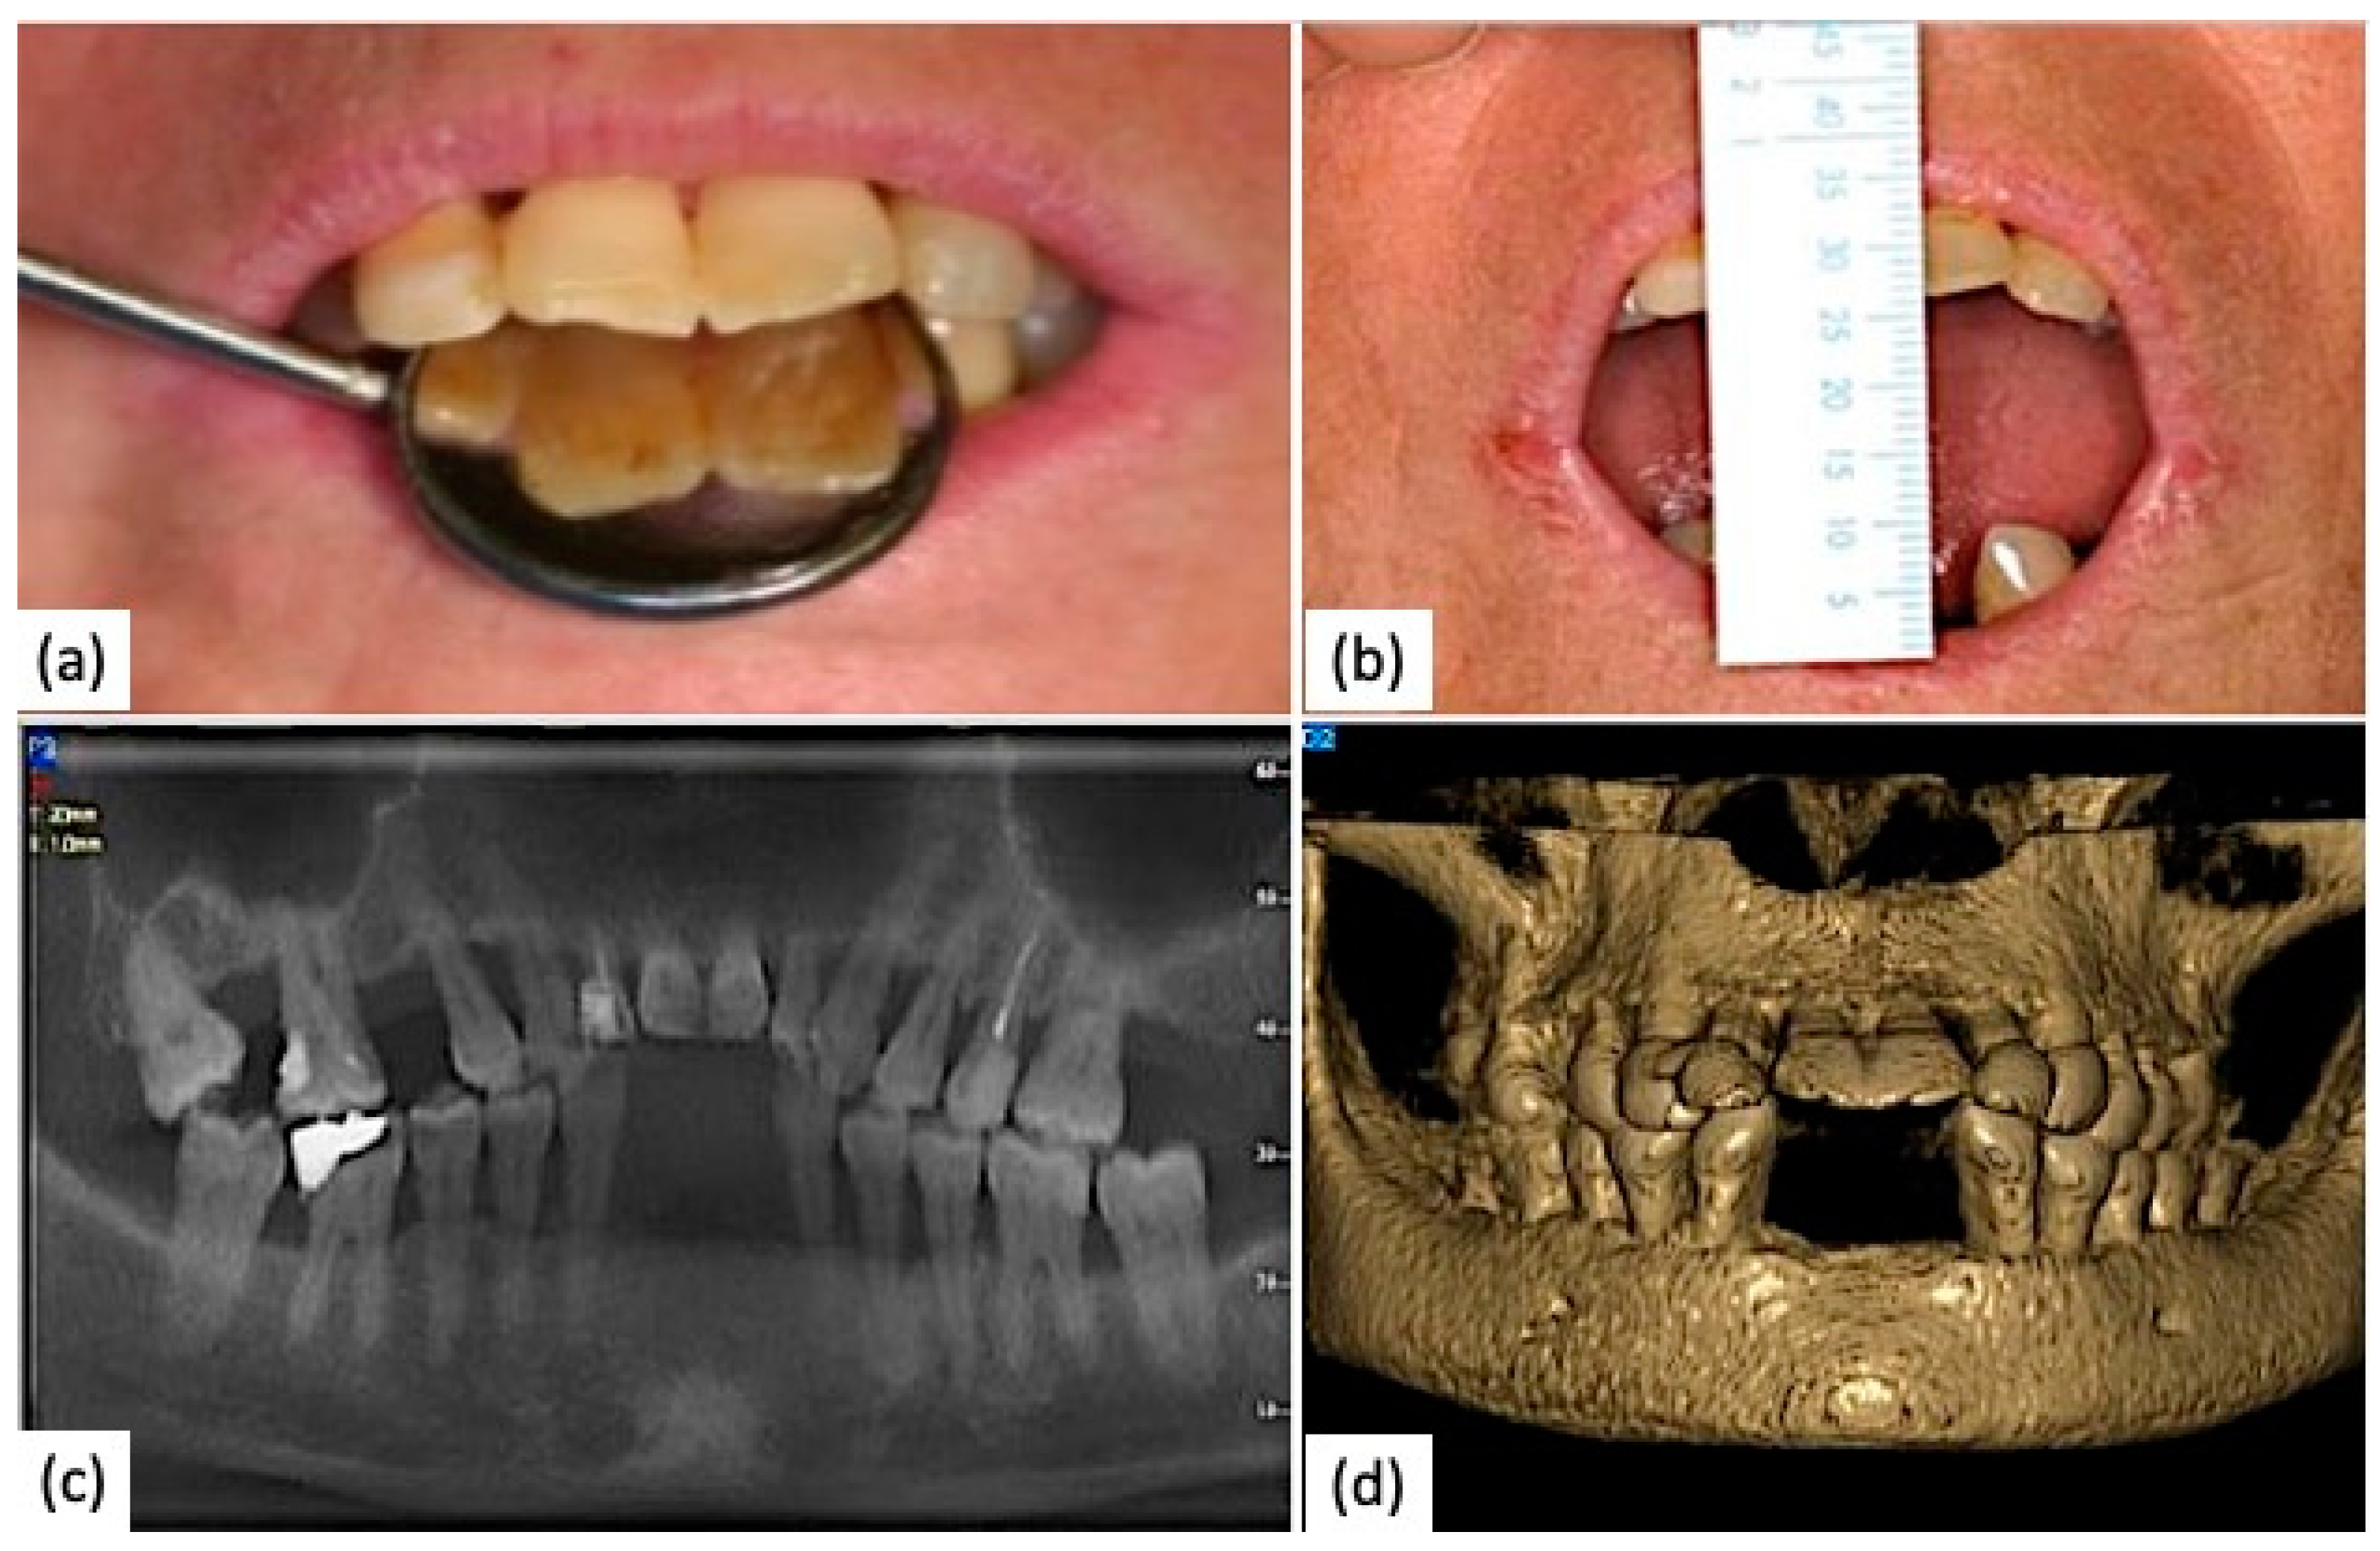

6. Clinical Case

- The degree of microstomia was measured by determining the distance between the incisal margins of the lower central tooth and the upper central tooth during the maximum oral opening.